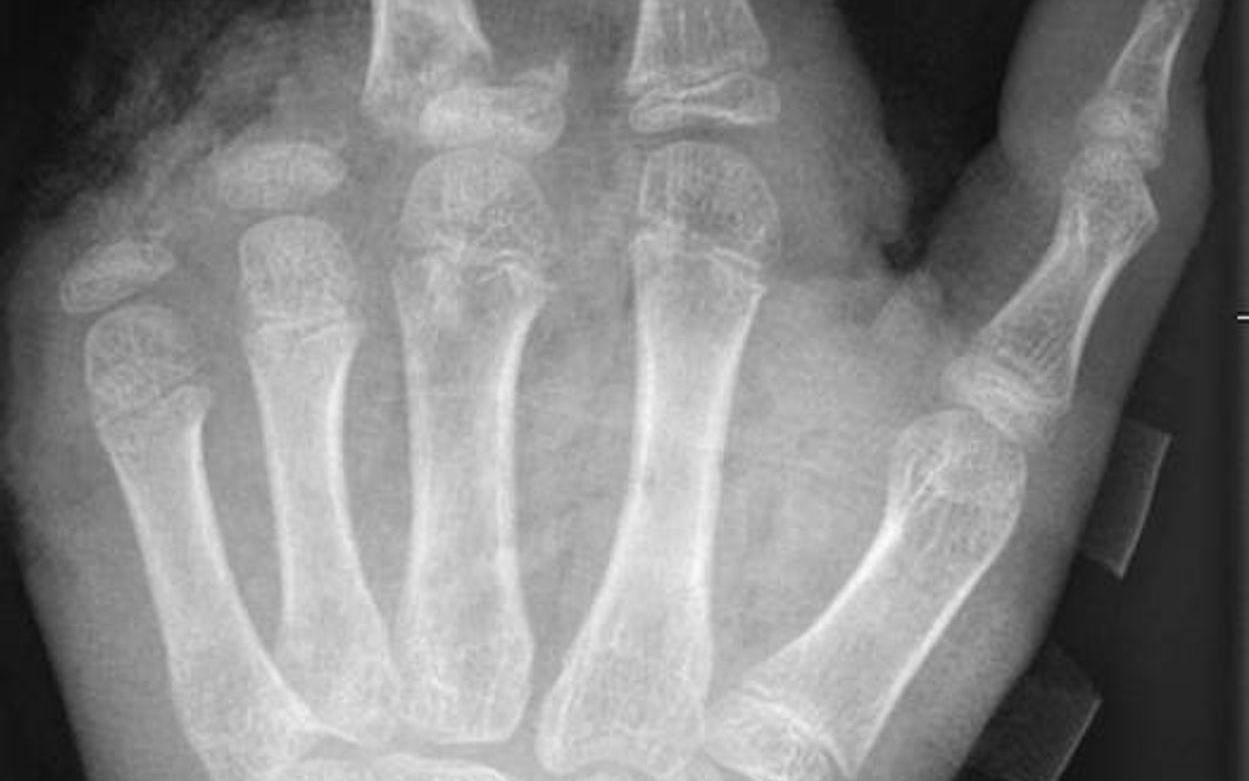

So kann ein Röntgenbild nach einer missglückten Böllerexplosion aussehen: Zwei Finger fehlen. © -/UKB/dpa

So kann ein Röntgenbild nach einer missglückten Böllerexplosion aussehen: Zwei Finger fehlen.